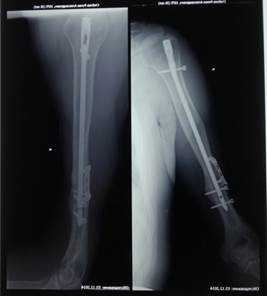

Больной С., 40 лет, госпитализирован в городскую больницу 24.12.2012 с сочетанной травмой после ДТП: закрытой черепно-мозговой травмой, сотрясением головного мозга, разрывом стенок толстой кишки, открытым переломом правой плечевой кости на границе ср/3 и н/3 со смещением отломков, травматической невропатией лучевого нерва. В экстренном порядке больному выполнены жизнеспасающие операции на органах брюшной полости. Первичный остеосинтез плечевой кости аппаратом внешней фиксации. Затем аппарат был демонтирован и выполнен окончательный реостеосинтез интрамедуллярным стержнем с блокированием. Послеоперационный период протекал без осложнений.

Через 4 мес. на контрольных рентгенограммах правой плечевой кости выявлен ложный сустав в зоне перелома. В неврологическом статусе – клиника полного нарушения проводимости правого лучевого нерва на уровне средней трети плеча. Активные разгибательные движения в правом лучезапястном суставе, пальцах правой кисти отсутствуют. По ЭНМГ выявлена грубая сенсомоторная дисфункция проведения по правому лучевому нерву.

Пациент госпитализирован в клиническую больницу № 122 им. Л.Г. Соколова, где 05.06.2013 г. выполнена операция – одновременная костная аутопластика ложного сустава правой плечевой кости и аутопластика большого дефекта лучевого нерва в средней трети плеча.

Под общим обезболиванием по старому послеоперационному рубцу, в средней трети, по наружной поверхности правого плеча, осуществлен доступ к плечевой кости, где обнаружен ложный сустав в месте перелома. Края кости обработаны, в них образован паз, куда был помещен отмоделированный фрагмент аутокости, предварительно взятый из гребня правой подвздошной кости. Костный аутотрансплантат фиксирован пластиной и 4 винтами.

С техническими трудностями в зоне перелома плечевой кости выделен центральный и периферический концы лучевого нерва. Центральный конец заканчивался невромой. После обработки концов нерва до отчетливых пучков, диастаз между ними составил 6 см. Выполнение состоятельного шва нерва с таким диастазом – не представлялось возможным. Для восполнения дефекта лучевого нерва решено произвести аутопластику. Для этого с правой голени из разреза длинной 2 см в области наружной лодыжки специальным инструментом взят икроножный нерв с образующими его ветвями. Между концами лучевого нерва, с использованием микрохирургической техники, вшито 4 аутотрансплантата из икроножного нерва, длинной по 7 см. Периферический конец лучевого нерва перекрыт полностью, а центральный на 3/4. Причем трансплантаты пришлось укладывать на металлическую пластину (рис. 1) и закрывать мягкими тканями.

На контрольных рентгенограммах правой плечевой кости – сросшийся перелом плечевой кости (рис. 3).

Рис. 3. На рентгенограмме больного С. сросшийся перелом плечевой кости